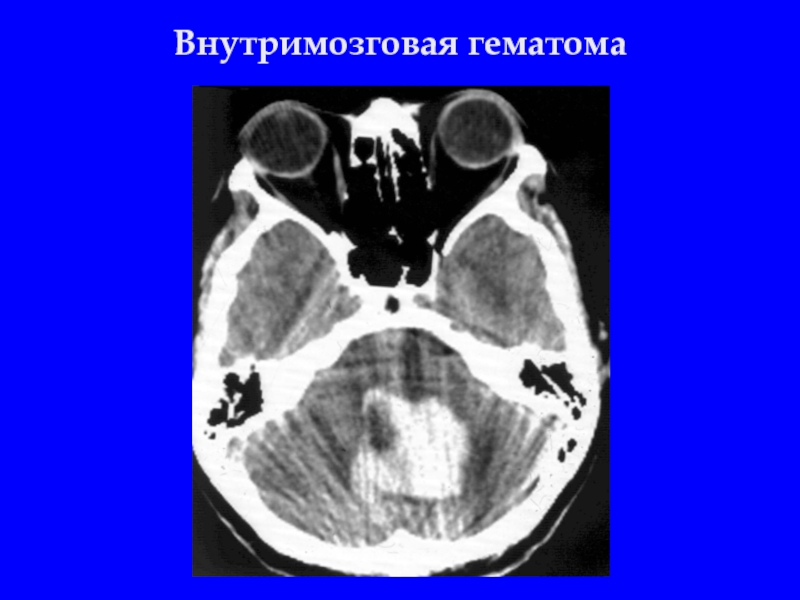

Слайд 19Внутримозговые гематомы (до 19%)

Слайд 22Внутримозговые гематомы

Контузионные очаги III-IV типа